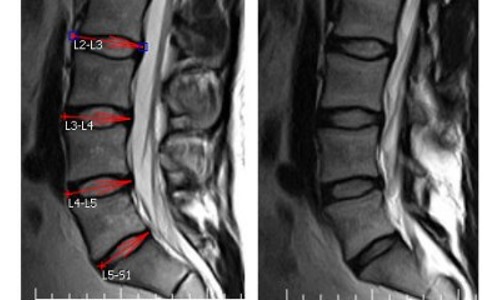

| Диагностика | МРТ (магнитно-резонансная томография) является «золотым стандартом» для выявления протрузий, рентген (для исключения других патологий), неврологический осмотр. | Точная диагностика позволяет определить степень протрузии и выбрать адекватное лечение. |

При первых признаках заболевания следует обратиться к неврологу. Специалист, оценив симптомы, назначит необходимые диагностические процедуры. В данном случае применяются рентгенография, компьютерная томография и магнитно-резонансная томография. Эти методы позволяют получить наиболее точные данные. С их помощью можно определить степень повреждения позвоночника и место расположения протрузии. Для более полной диагностики рекомендуется проводить обследование комплексно.

Например, компьютерная томография предоставляет меньше информации по сравнению с МРТ. Она не всегда может установить, влияет ли деформация на спинной канал и часто ошибается в оценке размеров выпячивания.

Магнитно-резонансное исследование, хотя и более сложное, предоставляет полную информацию о патологии. МРТ выявляет воспалительные процессы, различные изменения и наличие других заболеваний позвоночника.

Наиболее эффективным методом диагностики протрузии диска является МРТ.